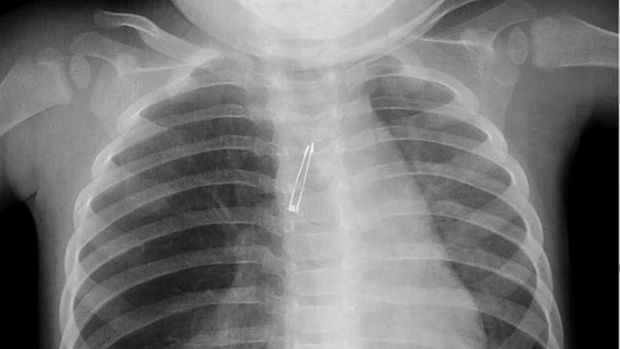

Awalnya, bayi tersebut mengalami batuk-batuk dan diberi obat batuk oleh dokter anak yang menganganinya. Namun setelah 3 hari, keluhannya tidak mereda dan bahkan mulai sesak napas. Ia pun dirujuk untuk pemeriksaan sinar X. Saat itulah baru ketahuan ada lampu LED di dekat paru-parunya.

"Benda tersebut bersarang di ujung saluran napas, dekat saluran utama menuju paru-paru kanan," kata Dr Kenneth Wong, dokter bedah anak dari Queen Mary Hospital in Hong Kong yang melaporkan kasus ini di jurnal BMJ Case Reports, seperti dikutip dari Livescience, Senin (14/9/2015).

Lampu LED akhirnya dikeluarkan dengan bronkoskopi, yakni alat seperti pipa dengan penjepit di ujungnya. Alat tersebut dimasukkan melalui jalan napas hingga mencapai lokasi objek yang akan diambil.

Material plastik pada lampu LED membuat benda tersebut sulit terdeteksi melalui pemindaian sinar X. Sementara pada anak-anak, komponen kecil pada mainan seperti halnya lampu LED memang rentan tertelan maupun terhirup.